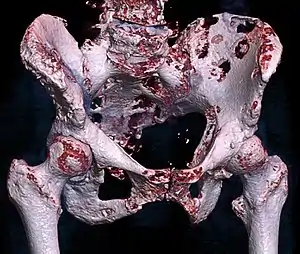

![]() | |

| 3D rendered CT scan of bone metastases of the hip bone, in a 60 year old woman with parotid gland cancer. Large lesions are seen on the ilium on the more distant side. Involvement of the vertebral column has caused a compression fracture. | |